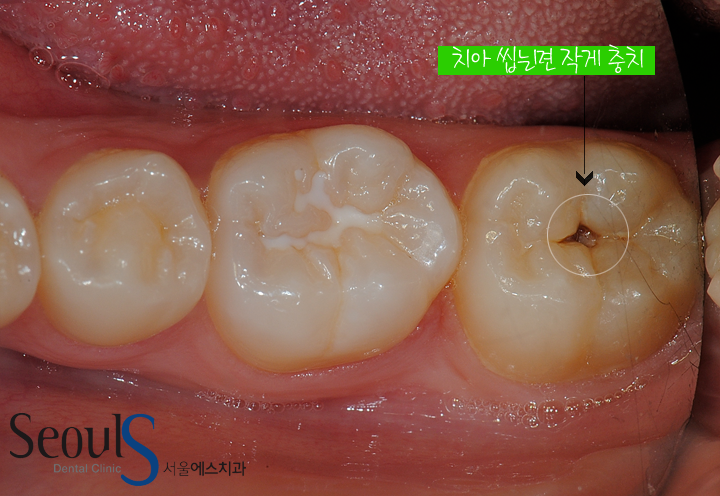

사진은 참고용이에요. 저렇게 흰색 이물질이 있는데 양치질을 해도 안사라지네요

가끔씩 아플때도 있습니다. 피곤하거나 할때 웅하는 느낌들면서 아픕니다 1 ~ 2 초 정도?

이게 혹시 충치인걸까요??

앞에 어금니는 실러트로 충치예방치료를 한것으로 보이고..뒤에 어금니는 충치로 보이고 치료가 필요할것 같습니다.